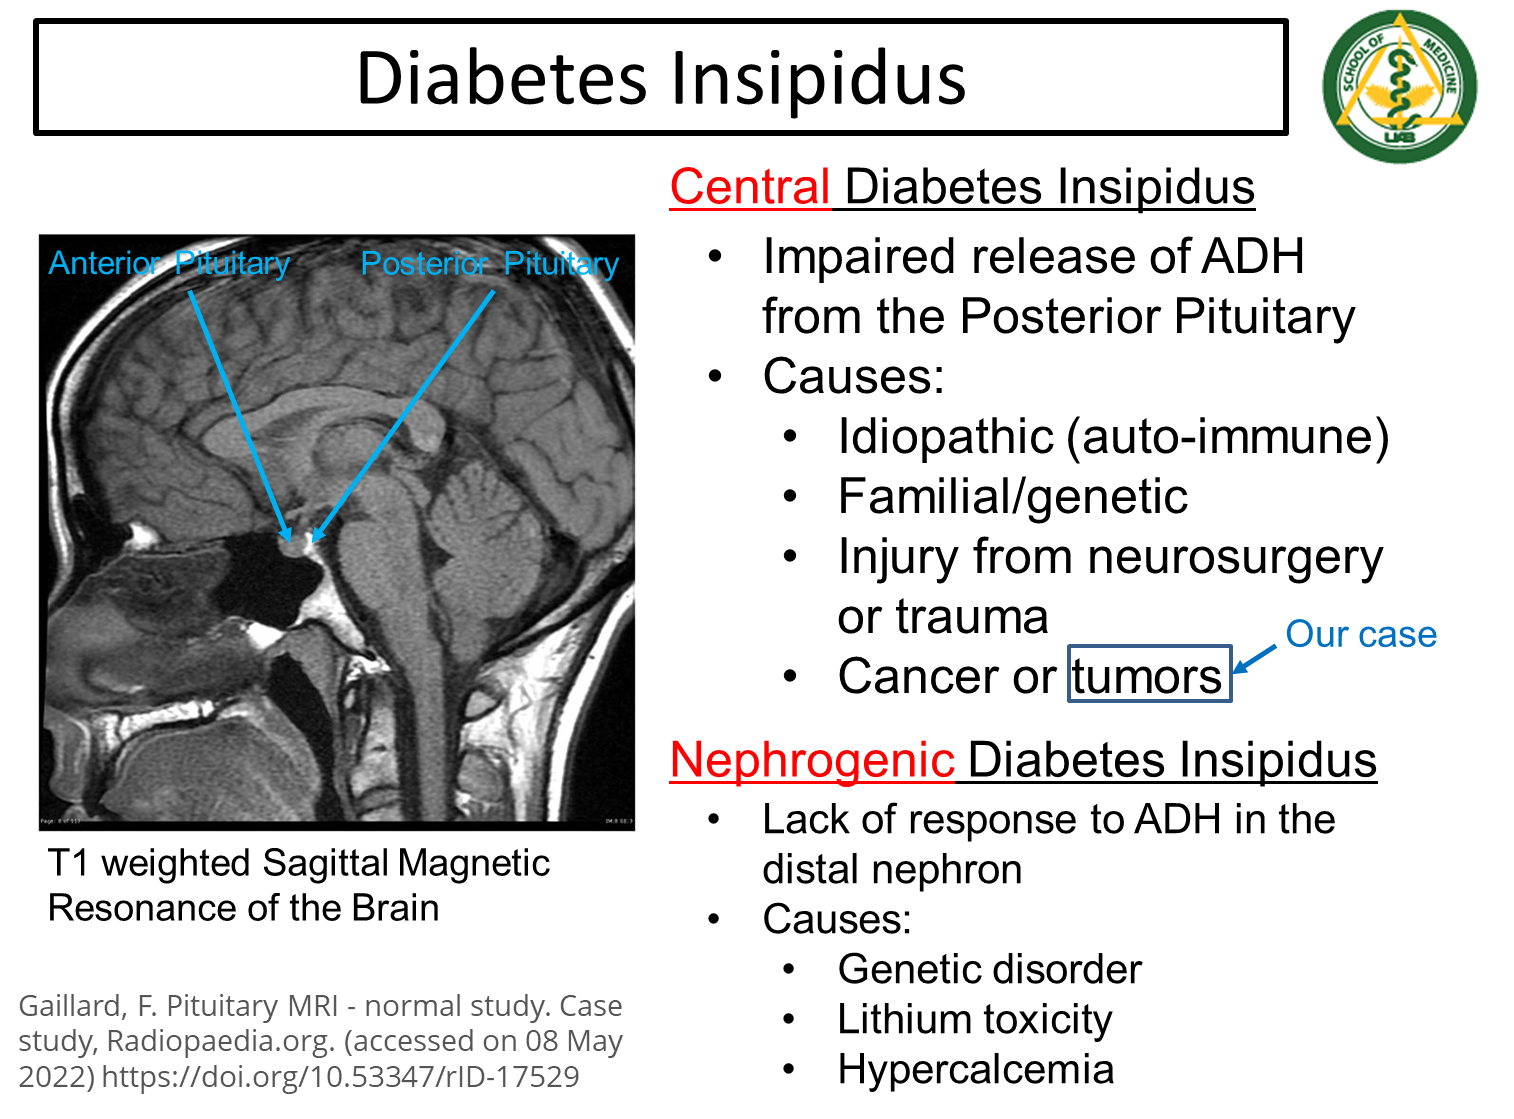

What is Diabetes Insipidus?

Diabetes Insipidus is a condition where ADH is not secreted or ADH is nonfunctional. Subdivided into Central and Neurogenic

→ results in a low urine osmolality even in a patient that should be expected to have high ADH levels and increased sodium reabsorption from the urine

1) Central

→ impaired release of ADH from the posterior pituitary gland and can be caused by a variety of issues

2) Nephrogenic

→ lack of response to ADH in the distal nephron